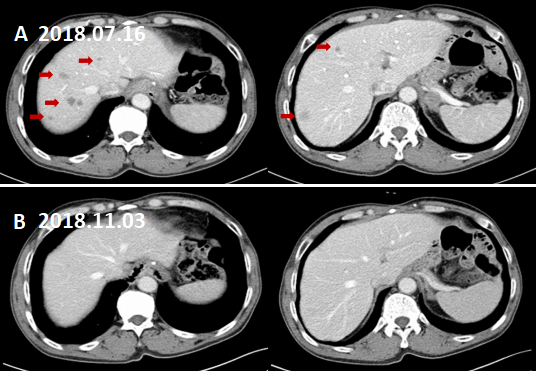

(2)全腹部CT增强扫描(2018.07.16):膈下淋巴结转移。左侧肾上腺区及腹膜后多发肿大淋巴结,转移考虑,较前片(2018.04.13)增多增大。肝内多发转移瘤。

图3. 膈下淋巴结转移。

A:术前CT增强(2017.06.08)B:术后CT增强复查(2017.07.26)示膈肌脚处未见肿大淋巴结;C:术后CT增强复查(2018.04.13)示左侧膈肌脚处新发肿大淋巴结。D:术后CT增强复查(2018.07.16)示左侧膈肌脚处肿大淋巴结与C相仿。

图4. 左肾上腺转移。

A:术前CT增强(2017.06.08)、B:术后CT增强(2017.07.26)、C:术后CT增强(2018.04.13)示左肾上腺增粗,增生考虑。D:术后CT增强复查(2018.07.16)示左肾上腺结节,约2.8×1.8cm,增强后不均匀强化,转移考虑。

全腹部CT增强扫描(2018.11.03):前片所示肝内多发低密度灶未见明显显示。左侧肾上腺区及腹膜后多发肿大淋巴结,转移考虑,较前片增多增大。

图7. 肝脏转移灶基本消退。

A:术后CT增强(2018.07.16)示肝脏多发转移灶。B:术后CT增强(2018.11.03)示肝脏转移灶基本消退。

图8. 左肾上腺区,膈下及腹膜后淋巴结较前增大增多。

术后CT增强(2018.11.03)B1示左肾上腺区转移灶较前片(2018.07.16)。A1略增大;B2,B3示膈下及腹膜后淋巴结转移较A2,A3增大增多。